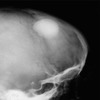

2

Metástasis (Ca mama)